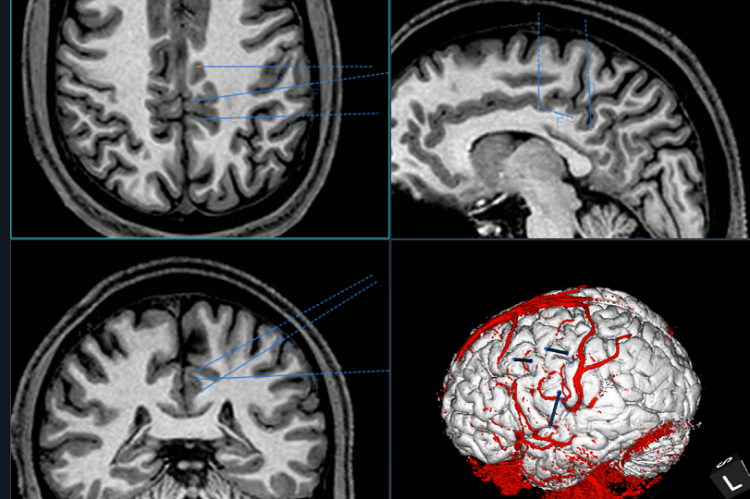

▲ 完善术前检查,并对手术进行规划

小周和家人经过慎重考虑后,决定接受SEEG手术。经过周密准备,手术由单峤主任、吴建珩副主任医师和王振博士团队实施。在神经外科手术机器人导航下,植入7根微电极,每根电极都精准的置入到靶点位置,术后复查CT并进行多模态三维重建,显示手术非常成功。通过后续治疗,小周癫痫发作已经较术前明显减少,现已康复出院。